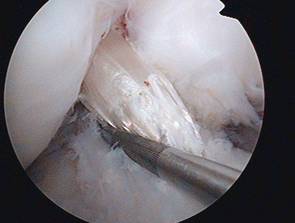

Kreuzbandersatzplastik